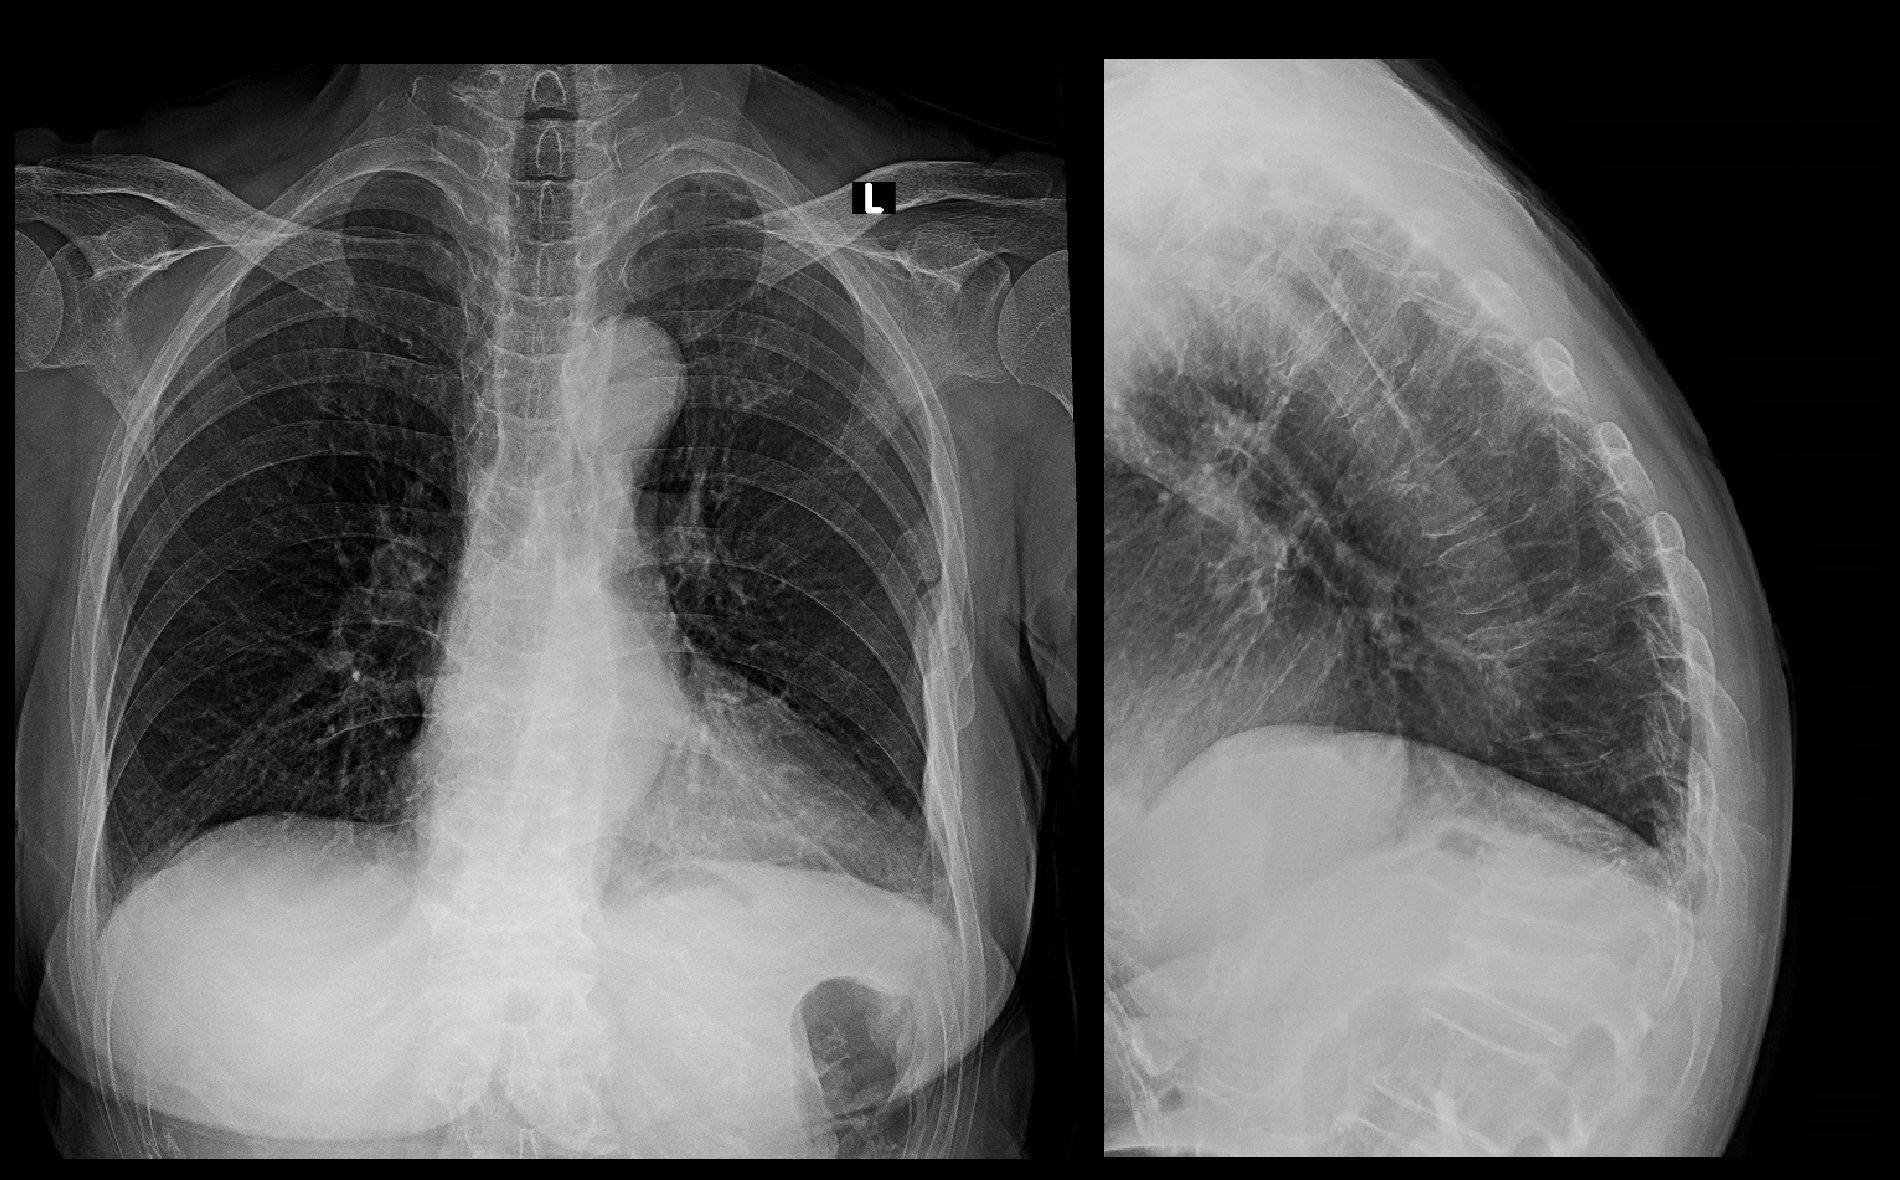

初診時Xp.jpg

当院初診時、レントゲン像では第12胸椎(Th12)が扁平化していることが確認できました。